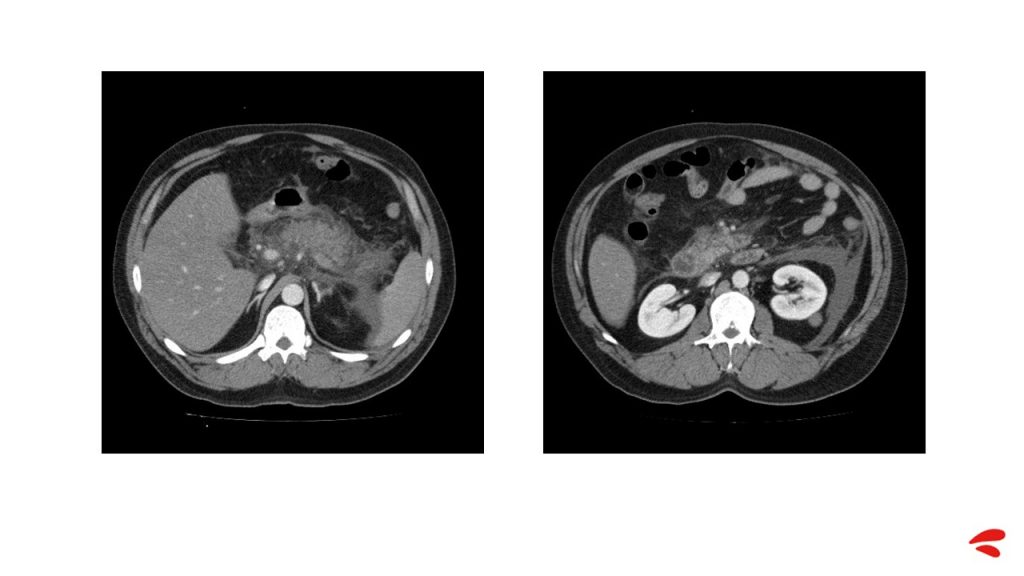

In view of these signs of peritoneal irritation, it was decided to perform an abdominal CT scan, which revealed acute necrotic pancreatitis, visible even without contrast infusion. A repletion defect in the superior mesenteric and splenic veins compatible with thrombosis was also visible, but no intra-abdominal collections were identified.

A repeat abdominal CT scan showed acute pancreatitis with acute peripancreatic necrotic collections, with glandular necrosis, and a previous venous thrombosis unchanged from the first test.